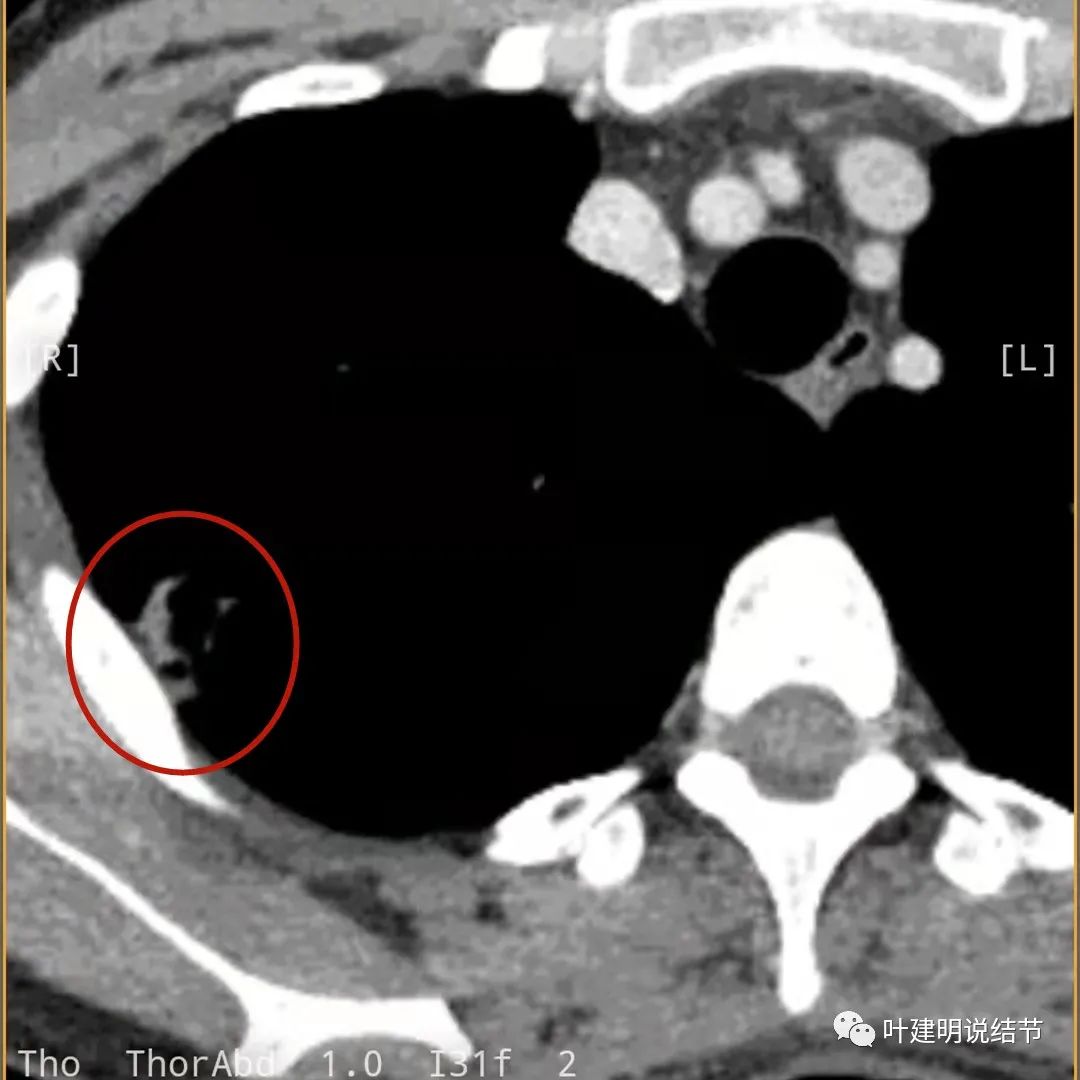

邻近胸膜增厚

主病灶此层面似三角形,邻近胸膜增厚(蓝色箭头),结节实性部分密度较高(粉色箭头),边缘显模糊(砖色箭头)